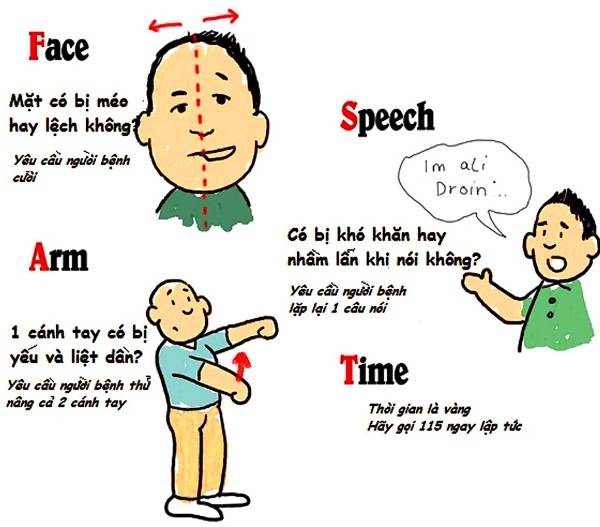

Bệnh đột quỵ có di truyền không; hoa mắt chóng mặt có phải là triệu chứng đột quỵ; làm sao phòng ngừa?...

Người bệnh tiểu đường có nguy cơ đột quỵ cao gấp 2-3 lần người khác, dấu hiệu thường nhầm với hạ đường huyết.